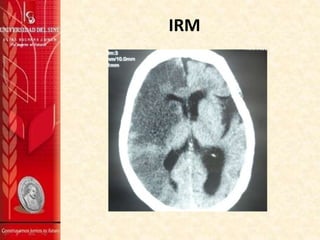

TOMOGRAFIA

normales , imagen de TAC deja ver cambios hiperagudos

que sugieren ACV isquémico en territorio de ACM derecha

Paciente en UCI con evidencia en imagen de TAC de ACV

isquémico, persiste con déficit neurológico descrito al

Imagen de control deja ver ACV hemisférico sin embargo

evolución clínica favorable y concepto de neuro cx descara

requerimiento de craniectomía decompresiva.